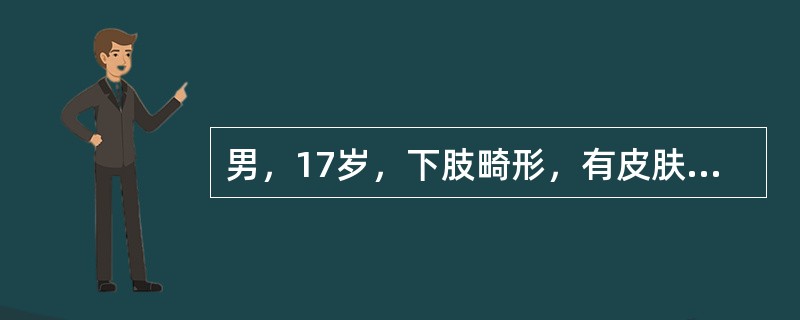

男,17岁,下肢畸形,有皮肤色素沉着,性早熟等,结合图选出最佳答案()

A.非骨化性纤维瘤

B.骨巨细胞瘤

C.骨纤维结构不良

D.内生软骨瘤

E.畸形性骨炎

[单选题]男,17岁,下肢畸形,有皮肤色素沉着,性早熟等,结合图像,最可能的诊断是()A.非骨化性纤维瘤B.骨巨细胞瘤C.骨纤维结构不良D.内生软骨瘤E.畸形性